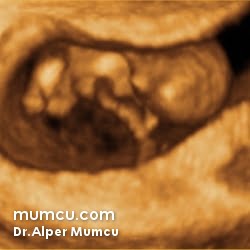

3 Boyutlu ultrason resimleri

Bu sayfadaki fotoğraflar degişik zamanlarda ve farklı hastalarda Dr. Alper Mumcu tarafından çekilmiştir.

10 haftalık gebelik